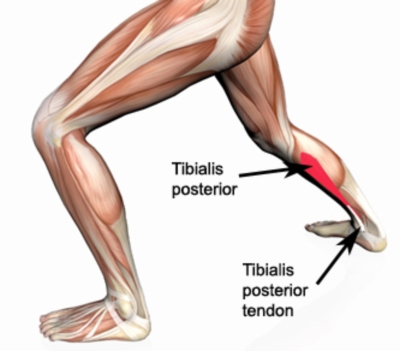

筋肉には必ず起始部と停止部が存在しておりますので、そのお話からです。後脛骨筋は下腿骨間膜、脛骨後面と腓骨内側面が起始部となり、下腿の大きな筋肉である腓腹筋とヒラメ筋よりも深いところを通り、長趾屈筋と長母趾屈筋の下を抜けて、内顆(うちくるぶし)の後ろを通り、舟状骨粗面と楔状骨、立方骨、第2〜4中足骨底に停止部を持ちます。

筋肉の機能としては距腿関節の底屈、距骨下関節の回外、ショパール関節の回外、底屈、内転、リスフラン関節の回外があります。舟状骨と楔状骨に付着しているということもあり、足部の内側の縦アーチを形成する役割も持っています。

そして、後脛骨筋は長腓骨筋と共にクロスサポートメカニズムを作り、横アーチを形成して足部の安定化にも一役かっています。この筋肉は底屈と回外が主な働きとなりますで、立位でのカーフレイズで十分に鍛えらえます。